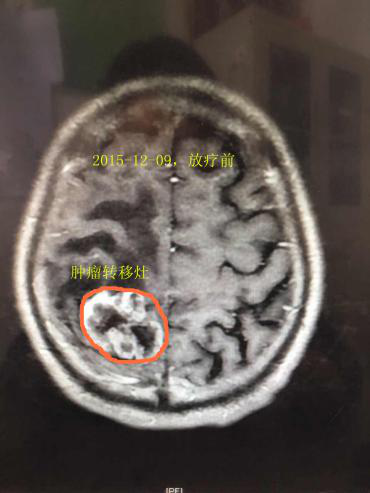

食管癌脑转移中位生存期半年左右,预后非常差;患者颅内肿瘤,已引起一侧肢体偏瘫,生活不能自理,对于家庭、对于社会都是巨大的负担,治疗的关键在于控制颅内转移瘤的进展。老爷子住院后,接诊的徐宜全副主任医师通过仔细的问诊、查体、核对相关检查资料,并综合科内讨论的结果,最终决定针对老爷子的头颅转移灶行三维适形放疗。而我院的医科达直线加速器系国际三大主流品牌之一,治疗精确、正常组织损伤小、肿瘤组织剂量高。在患者的坚持及我科医护人员的努力下,经过一个星期的治疗,患者头晕头痛逐渐缓解,自己就能拄着拐下床行走。

2016年8月,奇迹出现了!患者扔掉了拐杖,精神抖擞的来到医院,感谢放疗科全体医护人员,给他带来了新生!再次复查头颅MRI,颅内病灶完全消失,治疗效果显著。今年六月份我们再次随访了这位患者,杨大爷生活都能自理,活动自如。